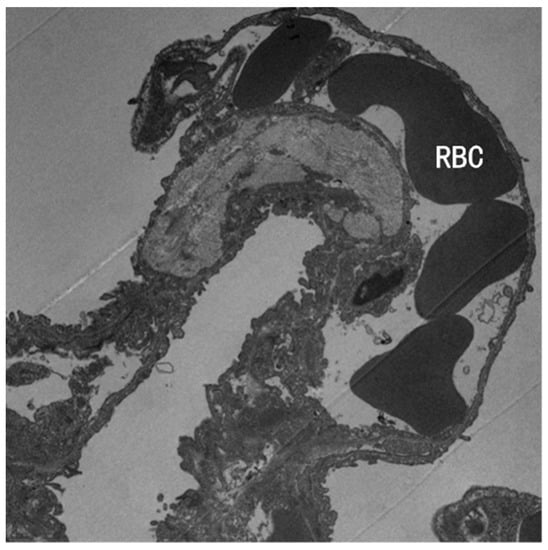

3.2. TEM Observation